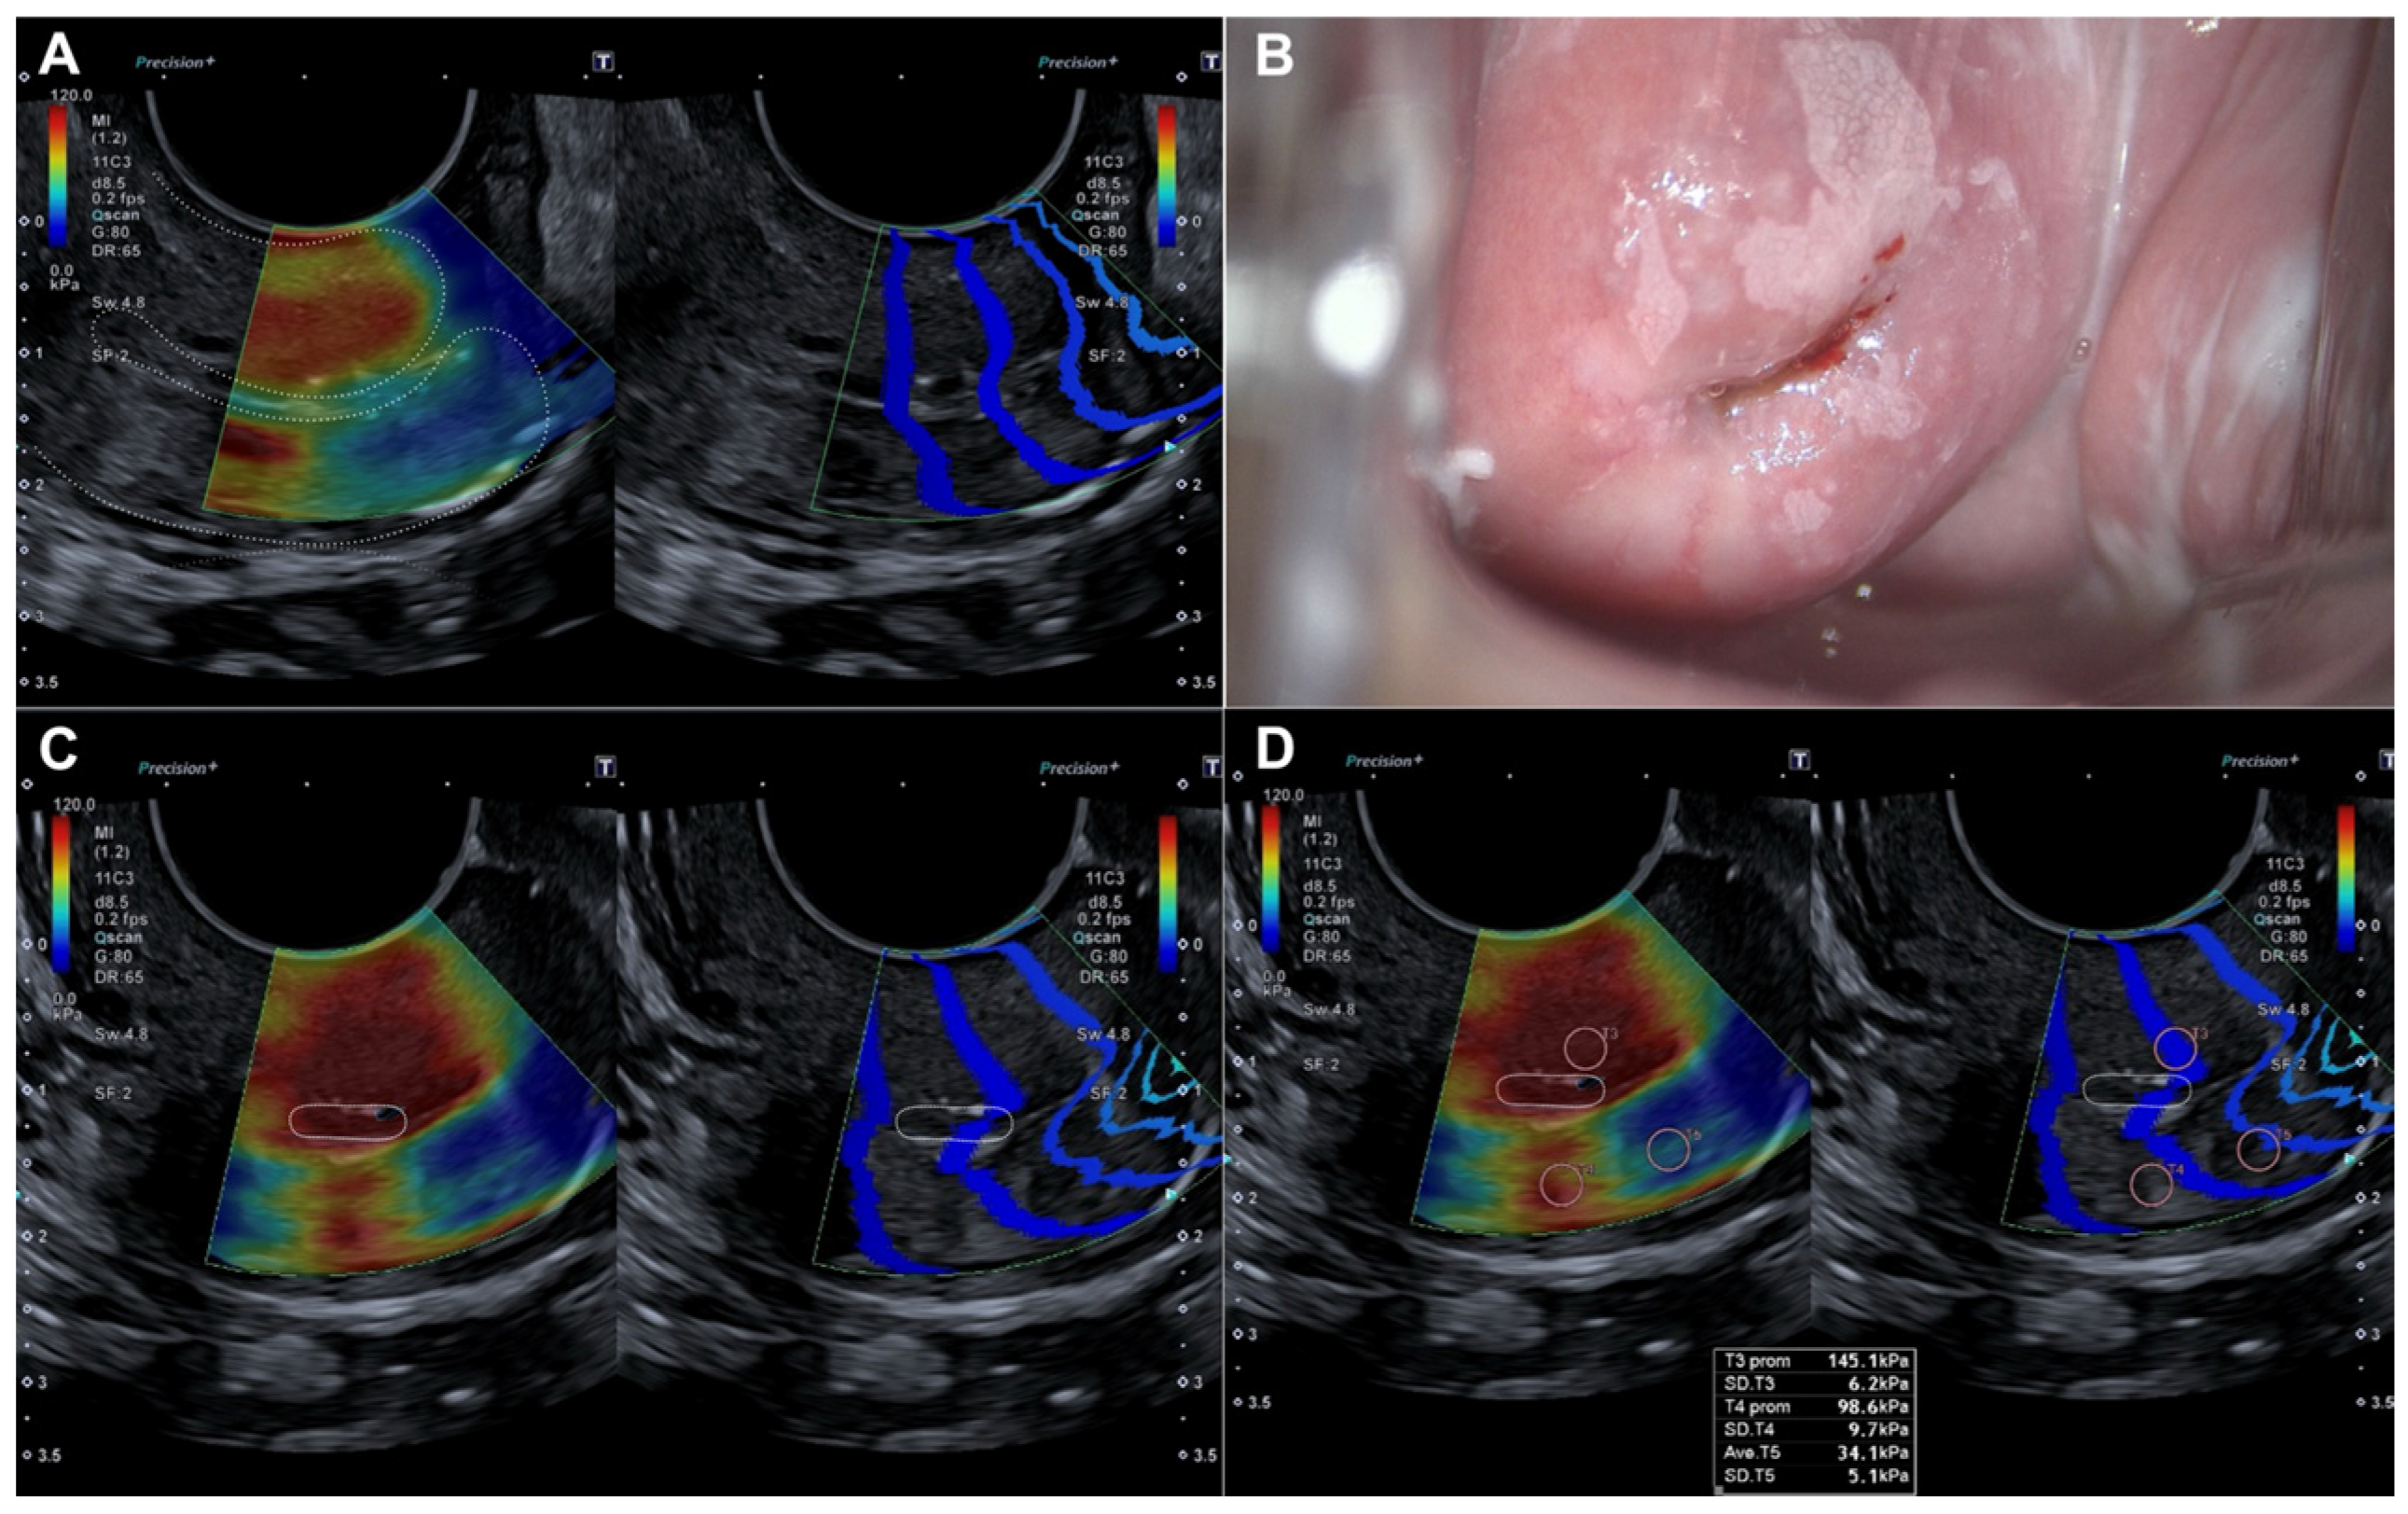

2.2.2. Evaluation Using SonoElastoColposcopy

- Sainz, J.A.; Castro, L.; Romo, J.M.; Holgado, A.; Fernández-Palacín, A.; García-Mejido, J.A. Evaluation of Pre-Malignant Lesions of the Uterine Cervix by Shear Wave Elastography: A New Diagnostic Tool. Ultrasound Med. Biol. 2021, 47, 3275–3282. [Google Scholar]

- Dudea-Simon, M.; Dudea, S.M.; Ciortea, R.; Malutan, A.; Mihu, D. Elastography of the uterine cervix in gynecology: Normal appearance, cervical intraepithelial neoplasia and cancer. A systematic review. Med. Ultrason. 2021, 23, 74–82. [Google Scholar] [CrossRef]

- Liu, C.; Li, T.T.; Hu, Z.; Li, Y.; Cheng, X.; Zhu, Y.; Lu, M. Transvaginal Real-Time Shear Wave Elastography in the Diagnosis of Cervical Disease. J. Ultrasound Med. 2019, 38, 3173–3181. [Google Scholar] [CrossRef]

| Exocervix (kPa) | 19.98 (±9.29) | 105.42 (±36.32) | p < 0.0001 |

| Endocervix (kPa) | 18.5 (±9.07) | 109.8 (±40.86) | p < 0.0001 |